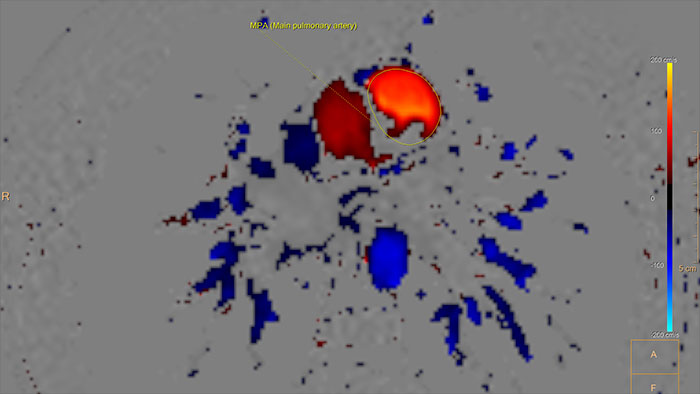

Wizualizacja i analiza ilościowa dynamiki przepływu krwi

Aplikacja MR QFlow umożliwia wizualizację i ocenę ilościową danych przepływu. Tworzone są dwuwymiarowe, kodowane kolorem mapy przepływu w formie nakładek na obrazy anatomiczne, wykorzystywane na przykład do obliczania objętości wyrzutowych. Aplikacja QFlow jest również integralną częścią pakietu MR Cardiac Suite, umożliwiając opisywanie badań w połączeniu z innymi narzędziami analitycznymi, takimi jak narzędzie do oceny czynnościowej.

Korzyści